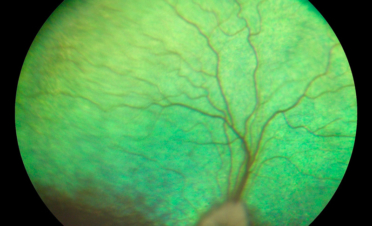

Ante la sospecha de un problema en el segmento posterior del ojo se recomendó la realización de pruebas adicionales que permitieran determinar la causa de su pérdida de visión:

En la angiografía fluoresceínica se apreció hiperfluorescencia del nervio óptico y en la periferia de la retina. Estas imágenes son compatibles con neuritis óptica y coriorretinitis.